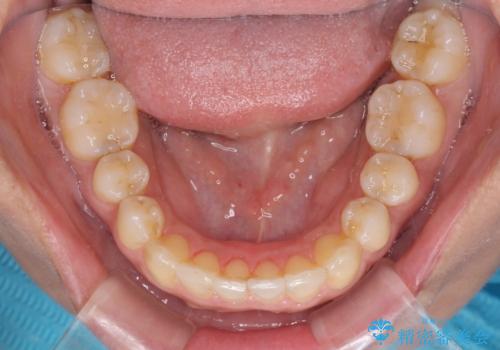

- 3年8ヶ月

- 治療費の目安: 85万円(税込)費用は治療当時の料金となります

通院途中に、仕事の都合で東京に来る機会が激減してしまったため、なかなか治療が進まず、当初終了予定であった時期が2年近くずれ込んでしまいました。

今後もむし歯治療が必要となるため、日程を調整して沖縄から通院されるとのことでした。